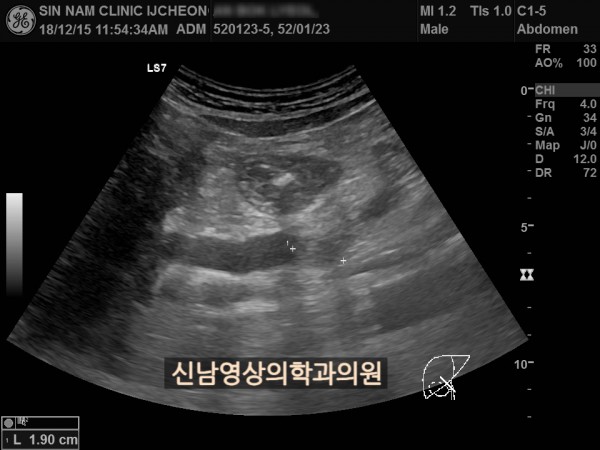

상복부 초음파 적용 사례

본 환자분은 50대 중반의 남성분으로 손가락안이 가렵다는 느낌으로 내원하셨습니다.

환자분은 황달 증세는 없었습니다.

빌리루빈 수치가 높아지면 소양증(가려움증)이 나타납니다.

피부의 밖이 아니라 속에서 느껴지는 가려움증으로 긁어도 해결되지 않는 것으로 복부 초음파 검사를 시행했고, 간내 담관들이 늘어나 있으면서 담도 하부에 혹이 발견되었으며, 이 혹은 담관밖으로 까지 퍼져있는 담도암으로 진단되었습니다.

간내 담관들이 확장되어 있을때는 담관을 막는 혹의 위치를 찾는 것이 중요하고, 이는 초음파 검사를 시행하는 의사의 숙련도가 갖춰져야 가능합니다.